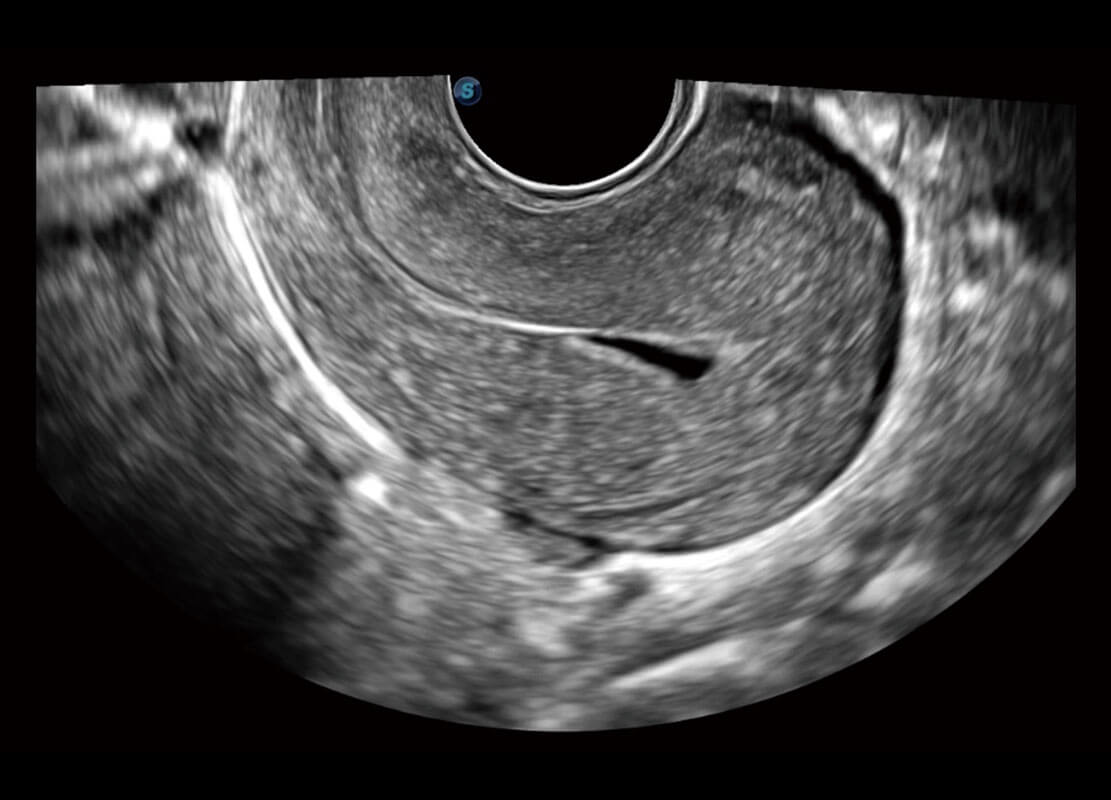

P60优异的图像质量搭载专科探头,在妇科基础疾病的诊断、卵泡生长的监测、输卵管通畅情况的判别等方面为您提供生殖应用方案。

• 腔内妇科-宫腔分离

• 腔内妇科-卵巢

• 腔内三维-宫内节育器

• 腔内三维-光影成像